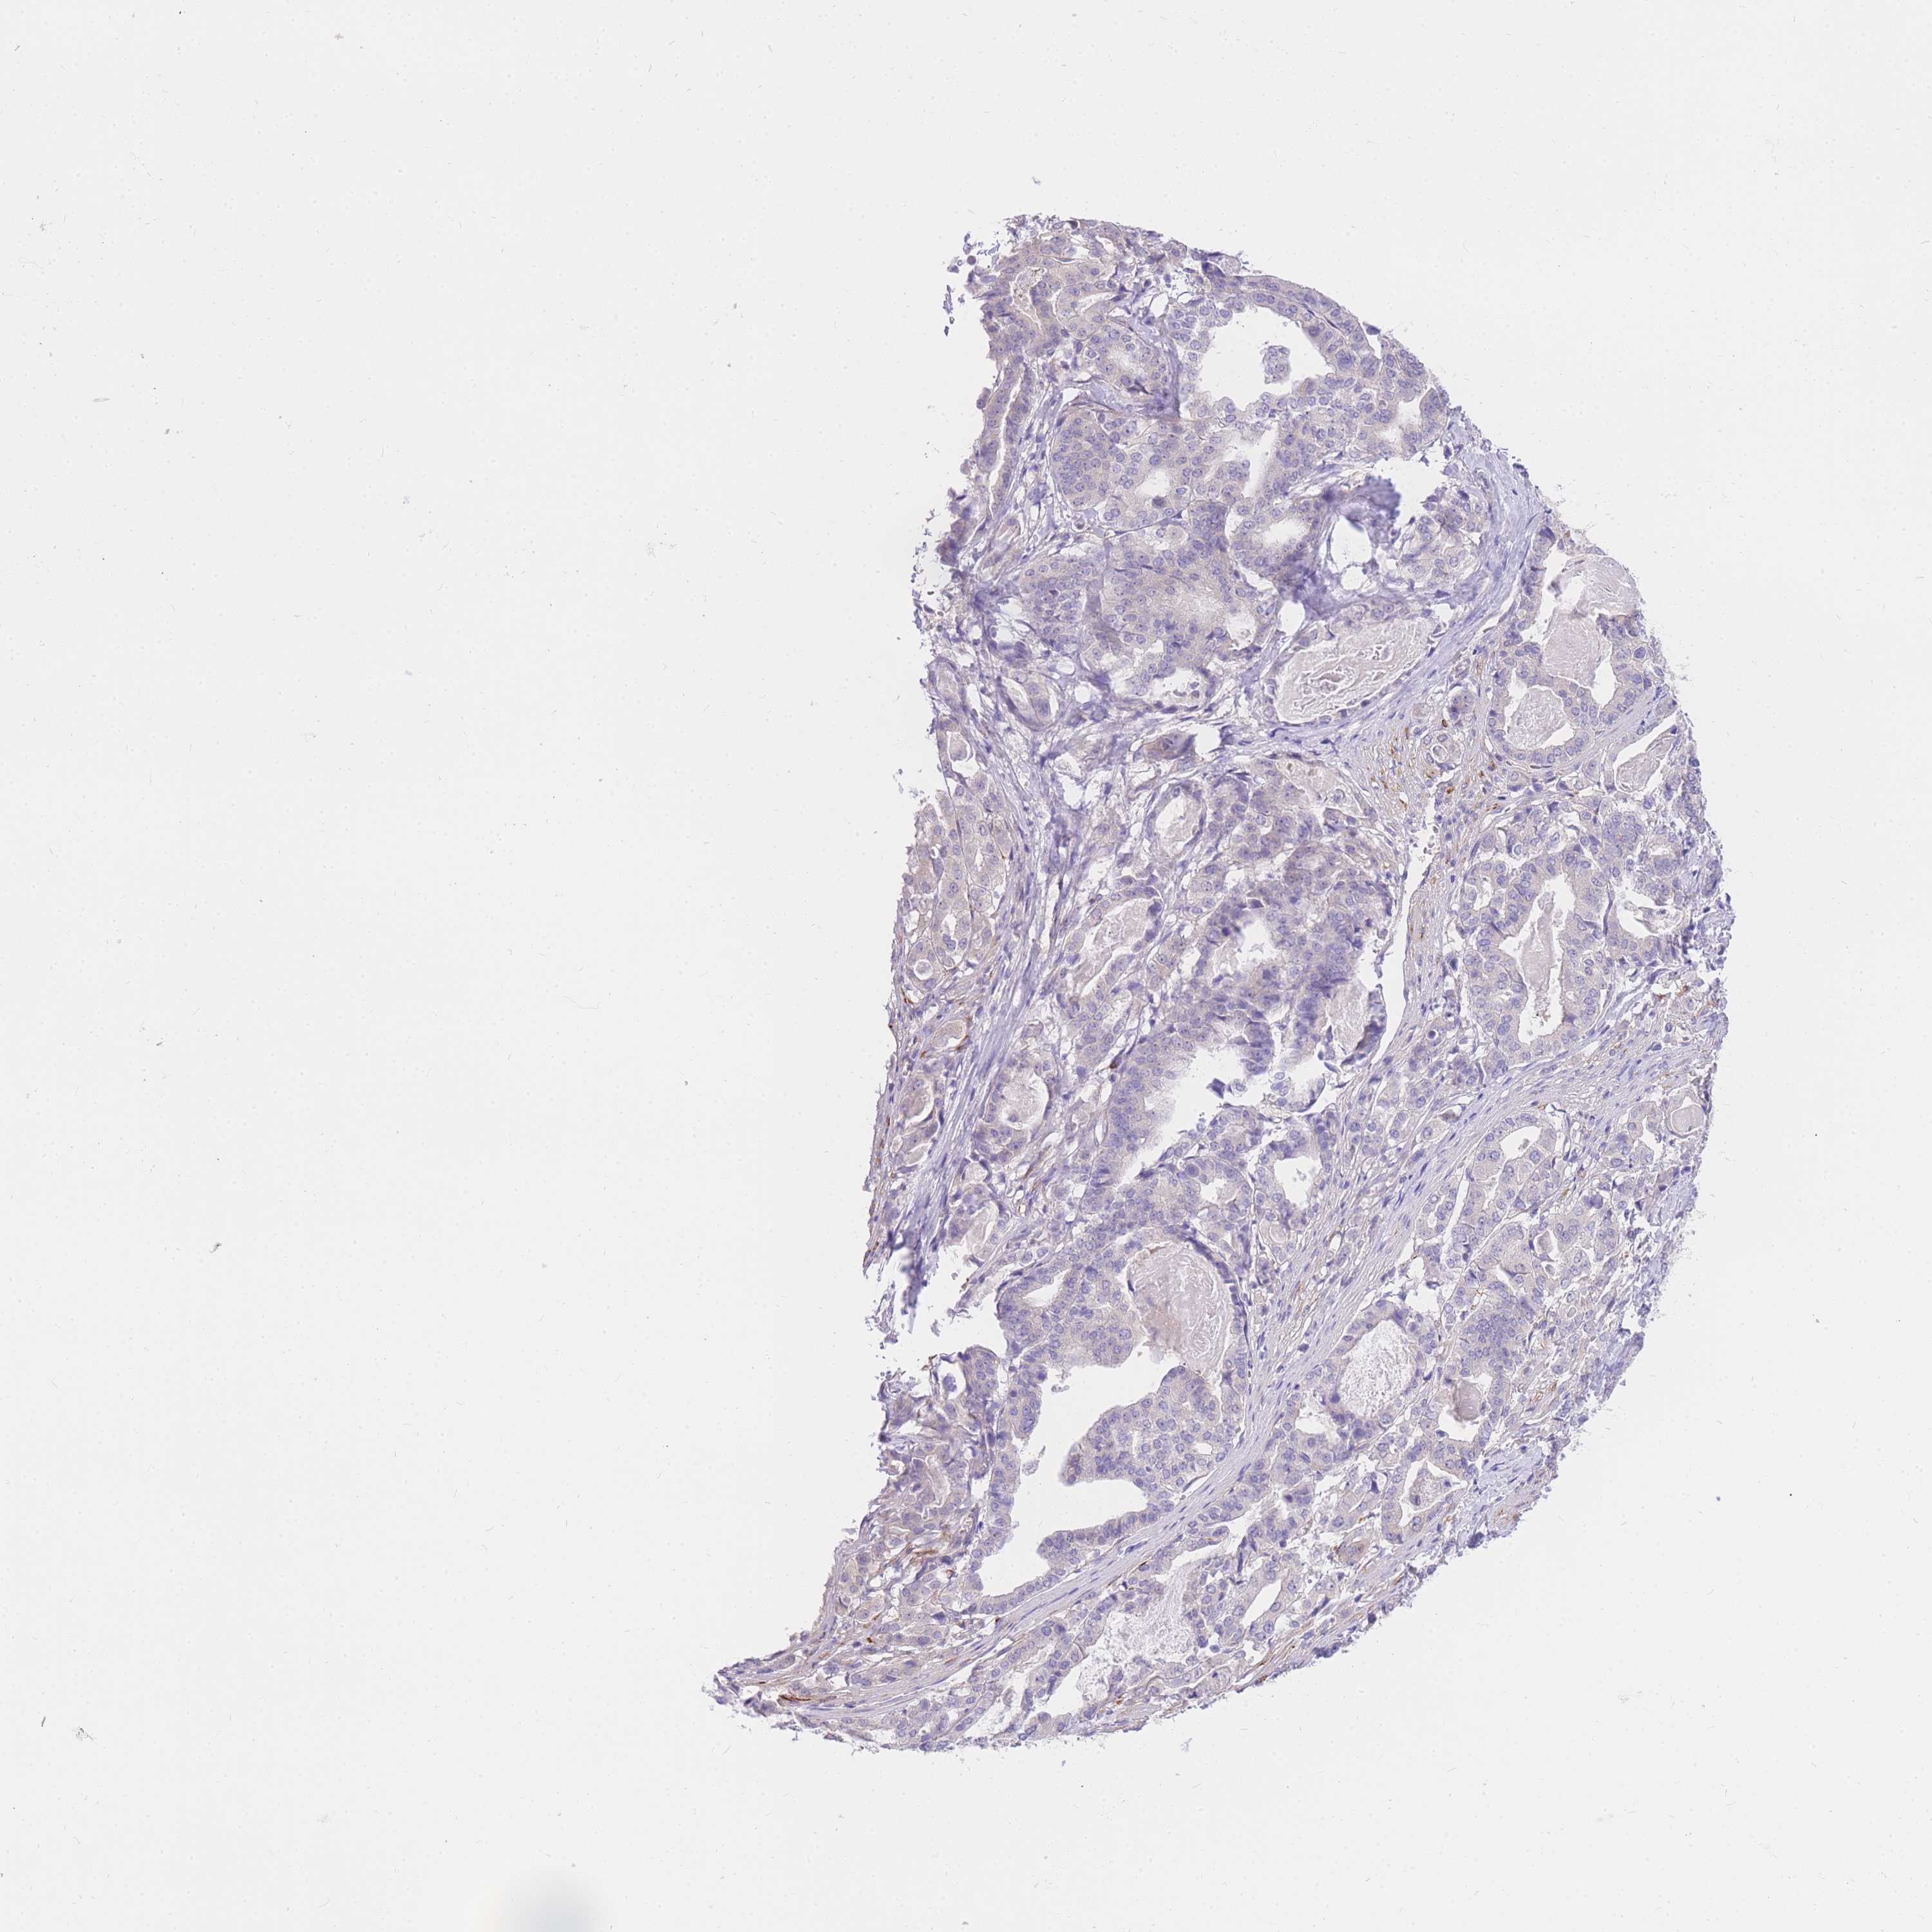

STOMACH CANCER - Protein expressioni

A mouse-over function shows sample information and annotation data. Click on an image to view it in a full screen mode. Samples can be filtered based on level of antibody staining by selecting one or several of the following categories: high, medium, low and not detected. The assay and annotation is described here.

Note that samples used for immunohistochemistry by the Human Protein Atlas do not correspond to samples in the TCGA dataset.

Antibody stainingi

Antibody staining in the annotated cell types in the current human tissue is reported as not detected, low, medium, or high, based on conventional immunohistochemistry profiling in selected tissues. This score is based on the combination of the staining intensity and fraction of stained cells.

Each image is clickable and will lead to virtual microscopy that enables deeper exploration of all samples and also displays staining intensity scores, fraction scores and subcellular localization as well as patient and tissue information for each sample.

Antibody HPA027242

Antibody HPA027328

Staining

High

Medium

Low

Not detected

Intensity

Strong

Moderate

Weak

Negative

Quantity

>75%

75%-25%

<25%

None

Location

Nuclear

Cytoplasmic/membranous

Cytoplasmic/membranous,nuclear

Adenocarcinoma, NOS